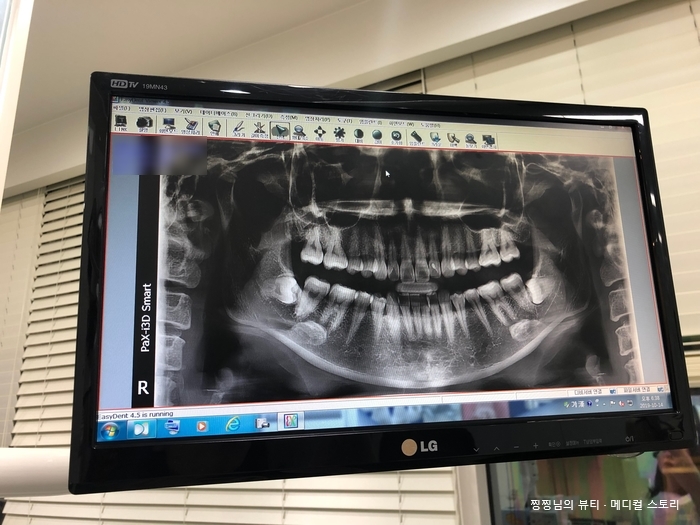

서울매스티지치과 스케일링+정기 치아검진

6개월에 한 번 정기 치아검진 강남 서울매스티지치과 안녕하세요~ 찡찡입니다! 병원은 꼭 꼭 잘 알아보고 ...